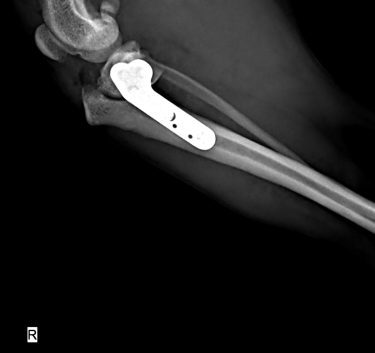

トイプードル(3.4kg)の前十字靭帯断裂に対するTPLO術(脛骨高平部水平化骨切術)☑

| 種類 | トイプードル |

| 年齢 | 12歳 |

| 診療科目 | 軟部外科・整形外科 |

| 症状 | 左後肢を挙上している。 |

触診では膝関節に腫脹と軽度の疼痛があり、前方引き出し試験(クラニアルドロアサイン)および脛骨圧迫試験でいずれも陽性反応を示しました。

レントゲン検査では膝蓋靭帯前方の脂肪パッドサイン(ファットパッドサイン)が明瞭で、関節内液貯留と軽度の関節炎変化を認めました。

これらの結果から、左前十字靭帯完全断裂と診断しました。